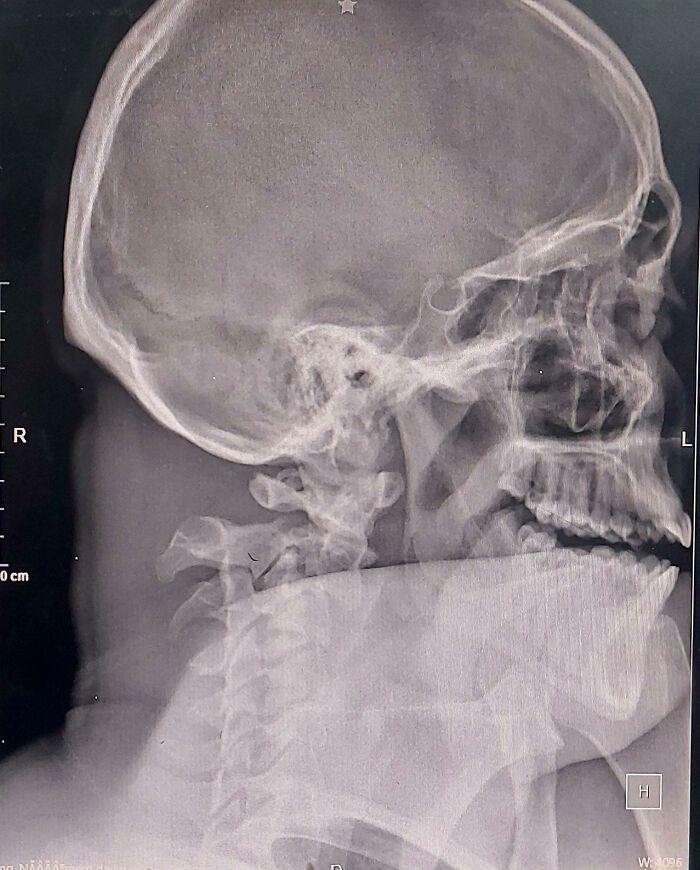

Man With 3-Inch Nail In Skull Goes To Hospital After Two Days… But Can’t Remember How It Got There!

When you nail something but can't remember how you did it.